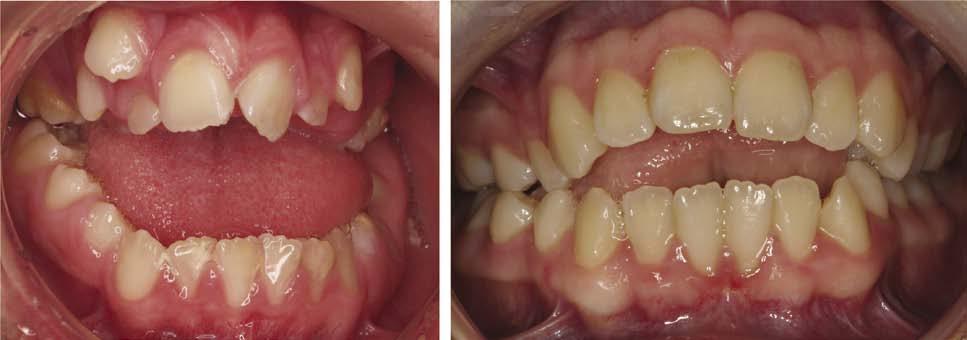

Gingivitis

Gingival irritation is inevitable with the use of fixed appliances, especially the placement of bands and this is exacerbated by poor oral hygiene, which can result in gingival hyperplasia. Gingival health improves significantly following the removal of appliances, with a reduction in probing depths mainly due to shrinkage of hyperplastic tissues (Fig. 1.18). Certain medications such as antiepileptic drugs and immunosuppressants in combination with poor oral hygiene can result in extensive gingival hyperplasia that can require gingival surgery following appliance removal.

1.18 Gingival hyperplasia during orthodontic treatment and subsequent improvement on removal of the appliance.

Figure